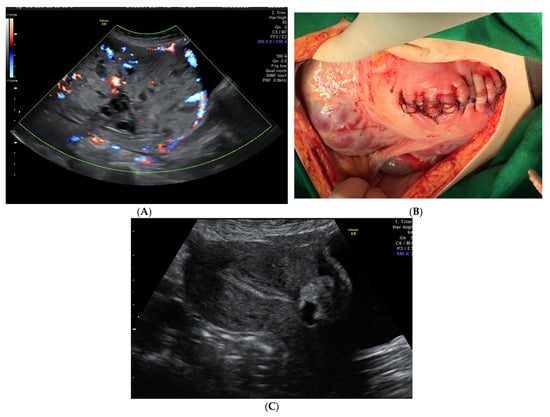

Figure 1.

(A). Ultrasound appearance of the placenta at 35 weeks of pregnancy. (B). Placenta left in situ and corporeal-fundal uterine suture at delivery. (C). Transabdominal ultrasound examination 27 weeks after delivery. On the anterior uterine wall, the small placenta is noted, and the endometrium is linear. The patient had a history of CS and, at 20 weeks, she was diagnosed with placenta previa with a high suspicion of anterior abnormal invasion to the urinary bladder. She had no vaginal bleeding. Planned Caesarean section was performed at 36 weeks of gestation, with a vertical mid-line incision chosen for the abdomen and a fundal incision of the uterus to avoid the upper pole of the placenta. After the delivery of the baby, the decision to leave the placenta in situ was taken to avoid significant bleeding and bladder injury. After the ligature of the umbilical cord close to its placental insertion, the uterine wall was sutured (B). Close monitoring was offered and, at 27 weeks after delivery, the placenta was almost fully evacuated (C) and the patient had normal menstruation.